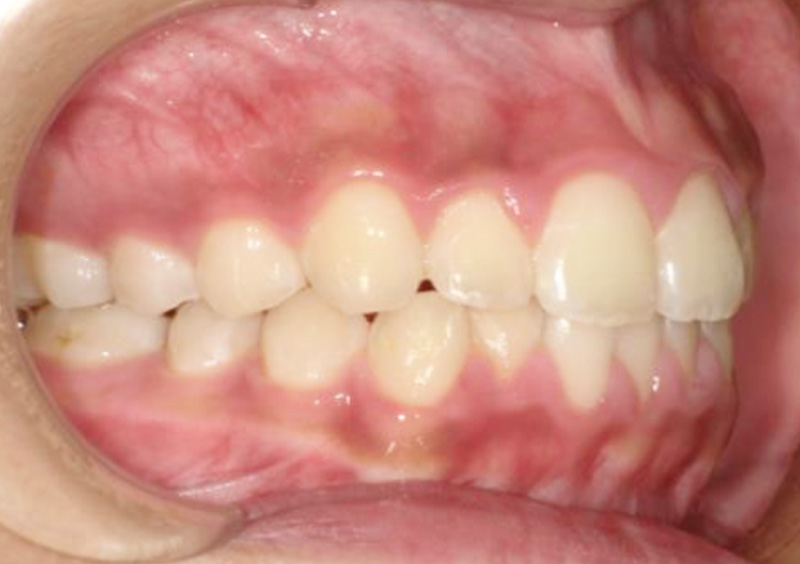

子供の矯正治療 大人の歯が生えてくるスペースがない 2025.10.21 【マルチブラケット矯正】大人の歯が生えてくるスペースがない 治療前 治療後 担当医 一瀬 悠依華 先生 主訴 大人の歯が生えてくるスペースがない 期間 2年3か月 費用 30万円(小児矯正) 治療内容 マルチブラケット装置(ホワイト) 治療に伴うリスク 歯根吸収、歯肉退縮 関連症例